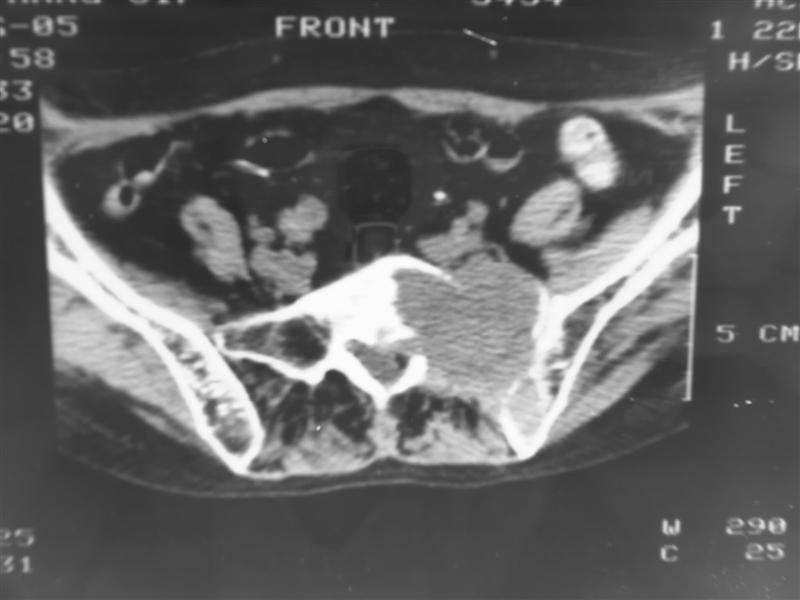

以下是引用老爱克斯新网客在2007-9-27 17:59:00的发言:[br]多个椎体及椎弓跟骨质破坏,并见软组织肿块,符合转移瘤改变,

以下是引用wqs571018在2007-9-27 16:48:00的发言:[br]支持:多发病变,骨质破坏伴软组织块影,符合转移.